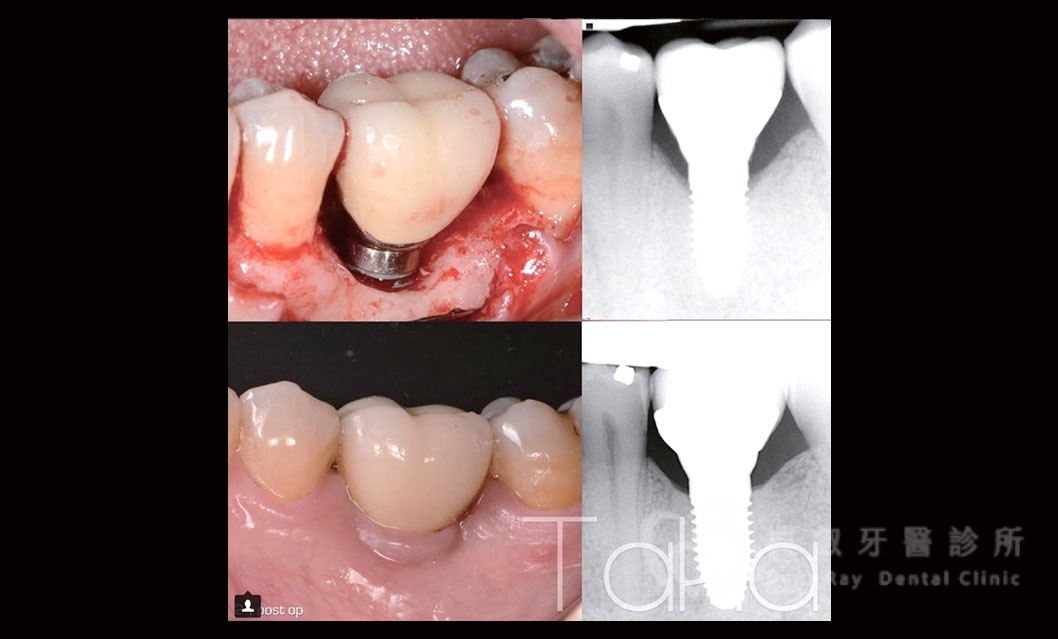

舊有植體失敗處理